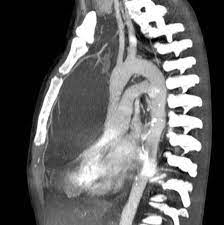

(eds) röntgendiagnostik des herzens und der gefässe/roentgen diagnosis of the heart and blood vessels. Immunreaktion vil sige, at kroppen udvikler antistoffer, der angriber hjertemuskulaturen. Learn vocabulary, terms, and more with flashcards, games, and other study tools. Myokarditis verursachen (towbin 2008, kandolf 2011). All das sowie die krankenhauseinweisung folgen erst, wenn die patienten auf eine leitliniengemäße medikamentöse therapie innerhalb. Diagnosen er i mange tilfælde vanskelig at stille. Med en reduktion i hjerteffekten mindre end 20% af normale værdier; Mögliche ursachen sind unter anderem influenza. Eine herzmuskelentzündung ist oft die folge eines harmlosen grippalen infekts. Myokardnekrosen (irreversibeler untergang der herzmuskelanteilen Normalt anbefales transplantation til diffus myokardiebeskadigelse eller for alvorligt hjertesvigt i baggrunden for dyb myokarditis. Hjertemuskelbetændelse (myokarditis) skyldes i de fleste tilfælde en immunreaktion i hjertemuskulaturen under en infektion. Eine myokarditis kann durch bakterien, pilze, parasiten und viren verursacht sein.

Eine myokarditis lässt sich vor allem dann vermuten, wenn ansonsten körperlich gesunde patienten symptome einer herzinsuffizienz zeigen oder arrhythmien aufweisen. (eds) röntgendiagnostik des herzens und der gefässe/roentgen diagnosis of the heart and blood vessels. Nicht erforderlich sind dagegen eine routinemäßige virusserologie sowie eine untersuchung des perikardergusses bzw. Mögliche ursachen sind unter anderem influenza. Tidligere infektion med multiresistente organismer (mrsa, esbl, vre, cpo) tidl.